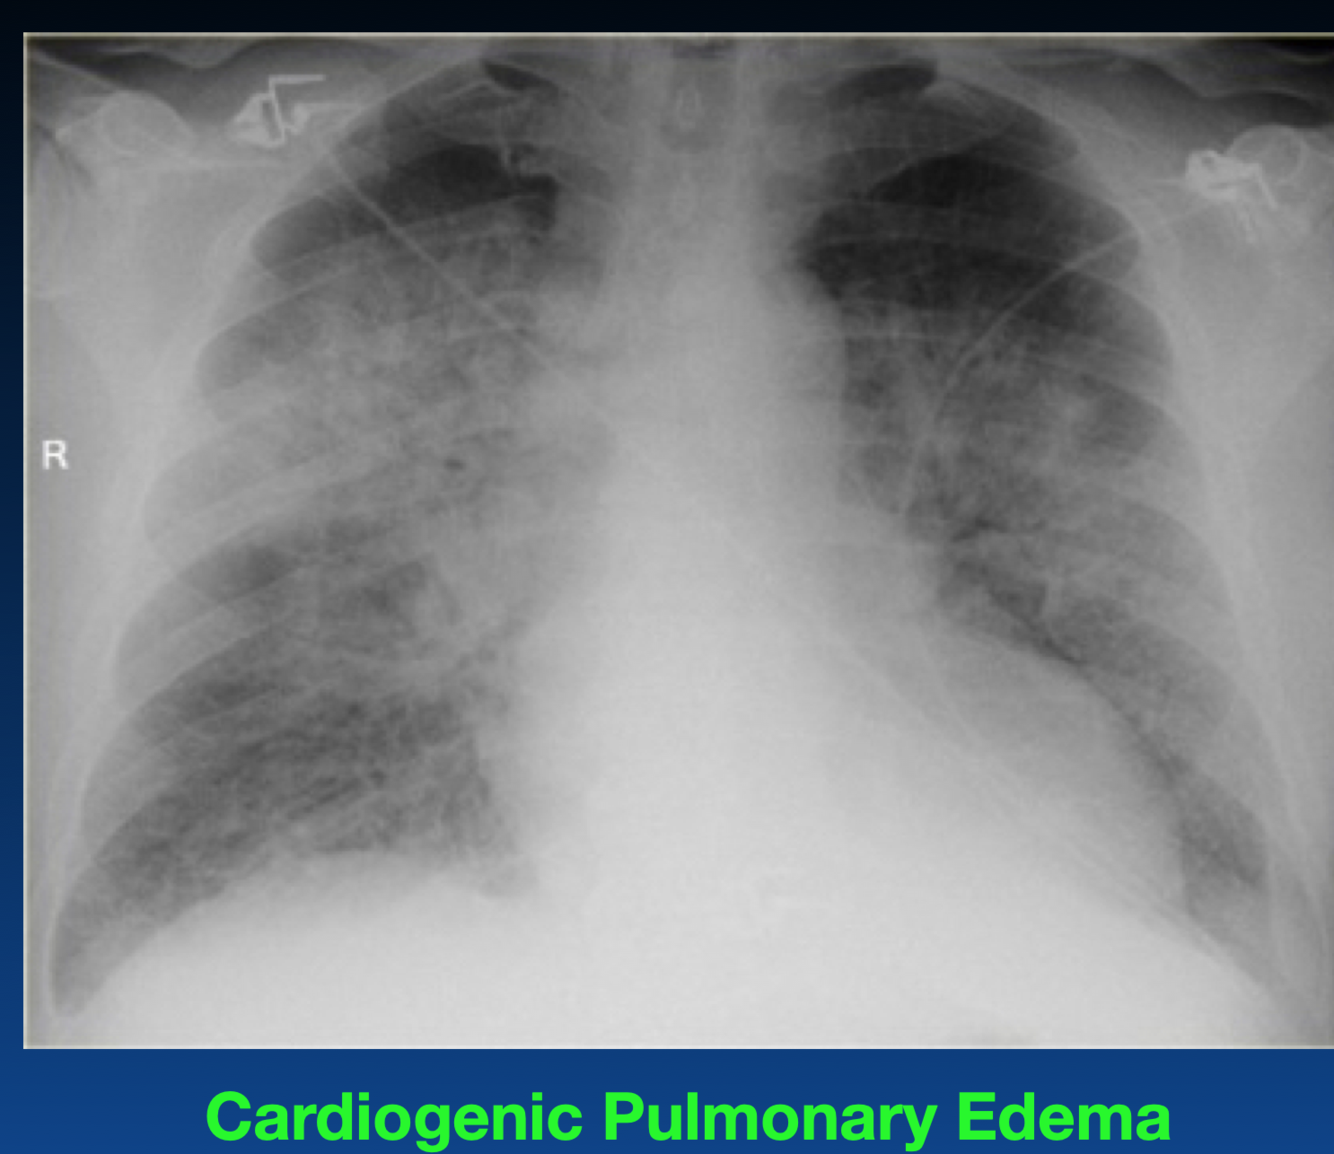

What occurs in this stage of CHF?